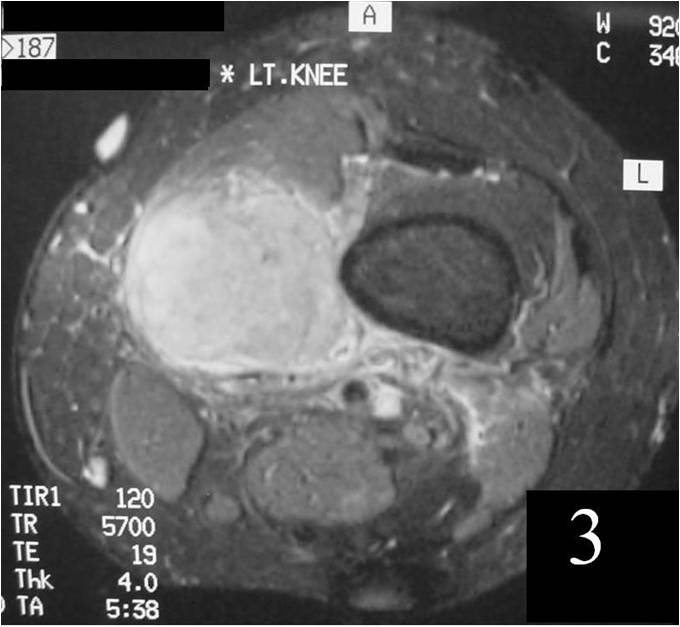

MRI

Nonspecific nonfatty mass (Fig. 2,3)

Large heterogeneous mass (Fig. 4, 5, 6)

Isointense to skeletal muscle on T1W

Usually heterogeneous on T2W SE

Fig. 4 MRI of a leiomyosarcoma of the forearm shows a mass isointense to muscle on T1W image, heterogeneous on T2W (Fig. 5) and enhances with contrast T1W fat suppressed (Fig. 6)